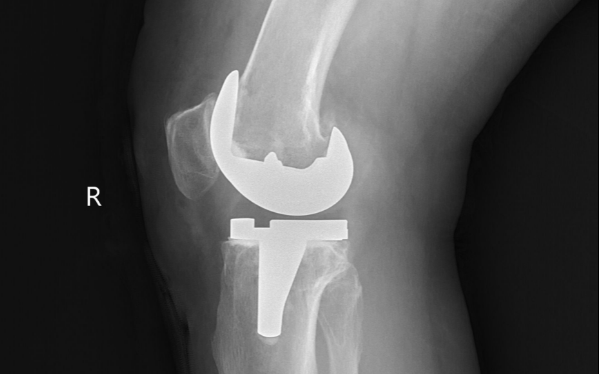

一般在骨折复位内固定、关节置换、脊柱手术等各类骨科手术后,及早开展康复是非常必要的。只有进行针对性、循序渐进的康复,才能逐渐解除运动受限,恢复肢体功能。

骨科术后康复最早可在术后当天进行,术后4-6周为黄金康复期,术后三个月内仍是骨科康复的最佳时段。

美全医疗集团葫芦岛中医康复医院骨伤康复中心采用各种中医传统疗法、作业疗法、运动疗法、各种物理疗法来进行骨科疾病的康复治疗。通过康复治疗,能提高患者的手术效果和生存质量,防止和减少患者因术后未及时做康复治疗、功能训练而造成的关节强直和功能障碍,是手术效果的重要保证,也是科室特色业务之一。